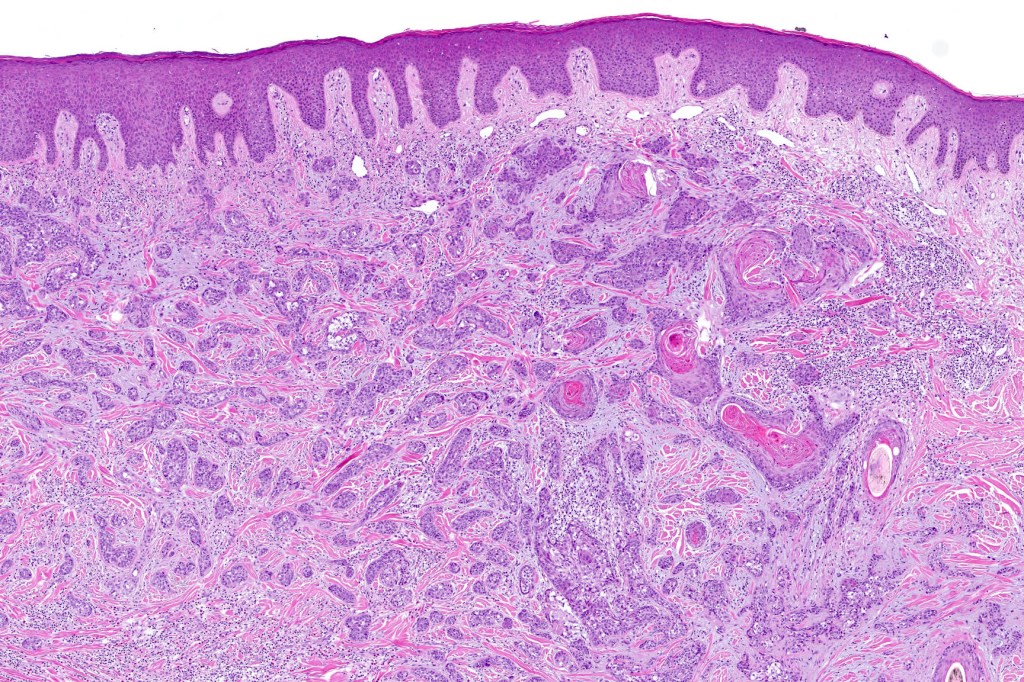

•Widely infiltrating biphasic tumor

•Superficial SCC

•Adenocarcinoma in deeper reaches

•Often extends to the subcutaneous fat